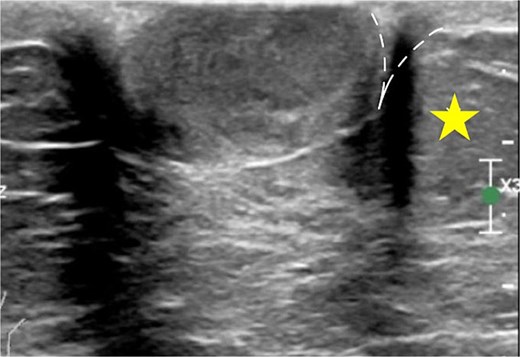

As the most common location of breast hidradenocarcinoma has been reported to be the nipple and subareolar region [2–9], mammography is often less sensitive in detecting these lesions, likely due to the increased density of the subareolar area [10]. In contrast, ultrasonography may be particularly useful in such cases. Due to its excellent spatial resolution, ultrasonography is the optimal modality for localizing superficial breast masses. Since superficial breast cancers arising from the anterior TDLU rarely occur entirely within the dermal layer, Giess et al. [10] have described the use of the dermal line identified on ultrasound to help determine the tumor’s origin. When a lesion is partially within the dermis, a ‘claw’ of dermal tissue wrapping around the margin of the lesion suggests a dermal origin (Fig. 3). This observation is based on the fact that intradermal tumors push the dermis downward, forming an acute angle with the dermal line, known as the ‘claw sign.’ In contrast, hypodermal lesions push upward against the dermis, forming an obtuse angle.

The claw sign. The ultrasonographic image shows a ‘claw’ of dermal tissue (dashed line) wrapping around the margin of the tumor and forming an acute angle. The star indicates the hypodermal layer.